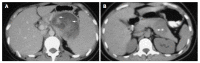

Results: Clinical presentation included a palpable abdominal mass in two patients and vague abdominal discomfort in another two. Two patients were asymptomatic; their tumors were found incidentally on abdominal sonographic examination for other reasons. The final patient was admitted with hemoperitoneum secondary to tumor rupture. The mean diameter of the tumors in the seven patients was 10.5 cm (range 5 to 20 cm). The lesions were located in the body and tail in five cases and in the head of the pancreas in two. Surgical procedures included distal pancreatectomy (3), distal pancreatectomy with splenectomy (2), pancreaticoduodenectomy (1) and a pylorus-preserving Whipple procedure (1). There were gross adhesions or histological evidence of infiltration to the adjacent pancreas and/or splenic capsule in four cases. None of the patients received adjuvant therapy. The mean follow up was 7 years (range 0.5 to 14 years). One patient developed multiple liver metastases after 14 years of follow up.